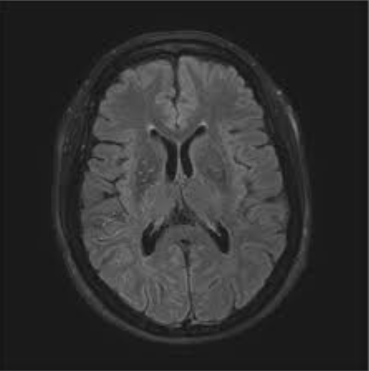

MRI scan of the brain

Special studies: MR Perfusion imaging

Diagnosis is made using imaging studies such as MRI, MR Angiography, CT scans, and cerebral angiography, which evaluate blood flow and detect narrowing of brain vessels with formation of collaterals appearing as ‘Puff Of Smoke’. Special MRI scans are used to understand the blood flow to the brain.